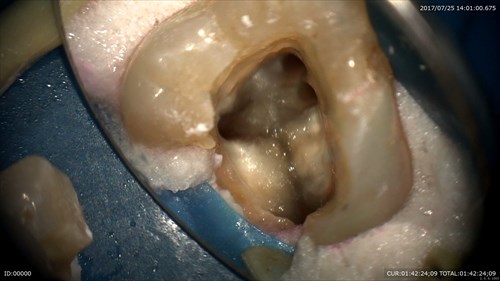

綺麗にして

根管充填